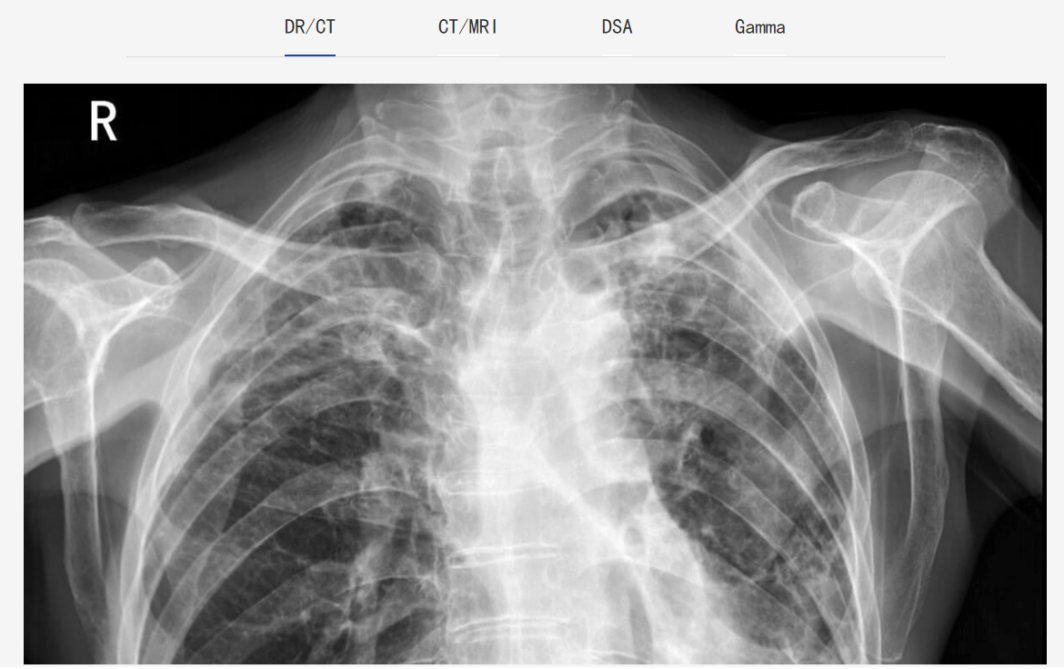

PACS全称为“影像归档和通信系统”,是基于现代计算机和通讯技术,用数字格式代替传统胶片进行图像处理,从而以高效率、高性价比来存放、管理、传送和显示医疗影像和病例信息的一种提供图像储存和访问的医疗影像技术。其主要任务就是把医院影像科日常产生的各种医学影像以数字化的方式海量保存起来,当需要的时候在一定的授权下能够很快的调回使用,同时增加一些辅助诊断管理功能。

简单来说,就是医疗影像诊断软件是关于医学影像处理,主要用于医学影像的二维和三维可视化和分析,而PACS是关于影像归档和通信。

睿显PACS影像传输系统基于放射、影像科医疗影像数据的获取、显示、传输及存储,系统采用业界先进、成熟的软件开发技术和系统结构,严格遵循DICOM3.0、HL7、IHE等国际标准与规范,围绕着实现全院影像科室全面覆盖、影像业务无纸化应用、数据存储一体化的目的,为医院提供稳定、安全、便捷的信息服务。

将睿显PACS影像传输系统与医疗影像诊断软件相结合,能提升办公及管理效率,利于资源信息的集中管理及利用。